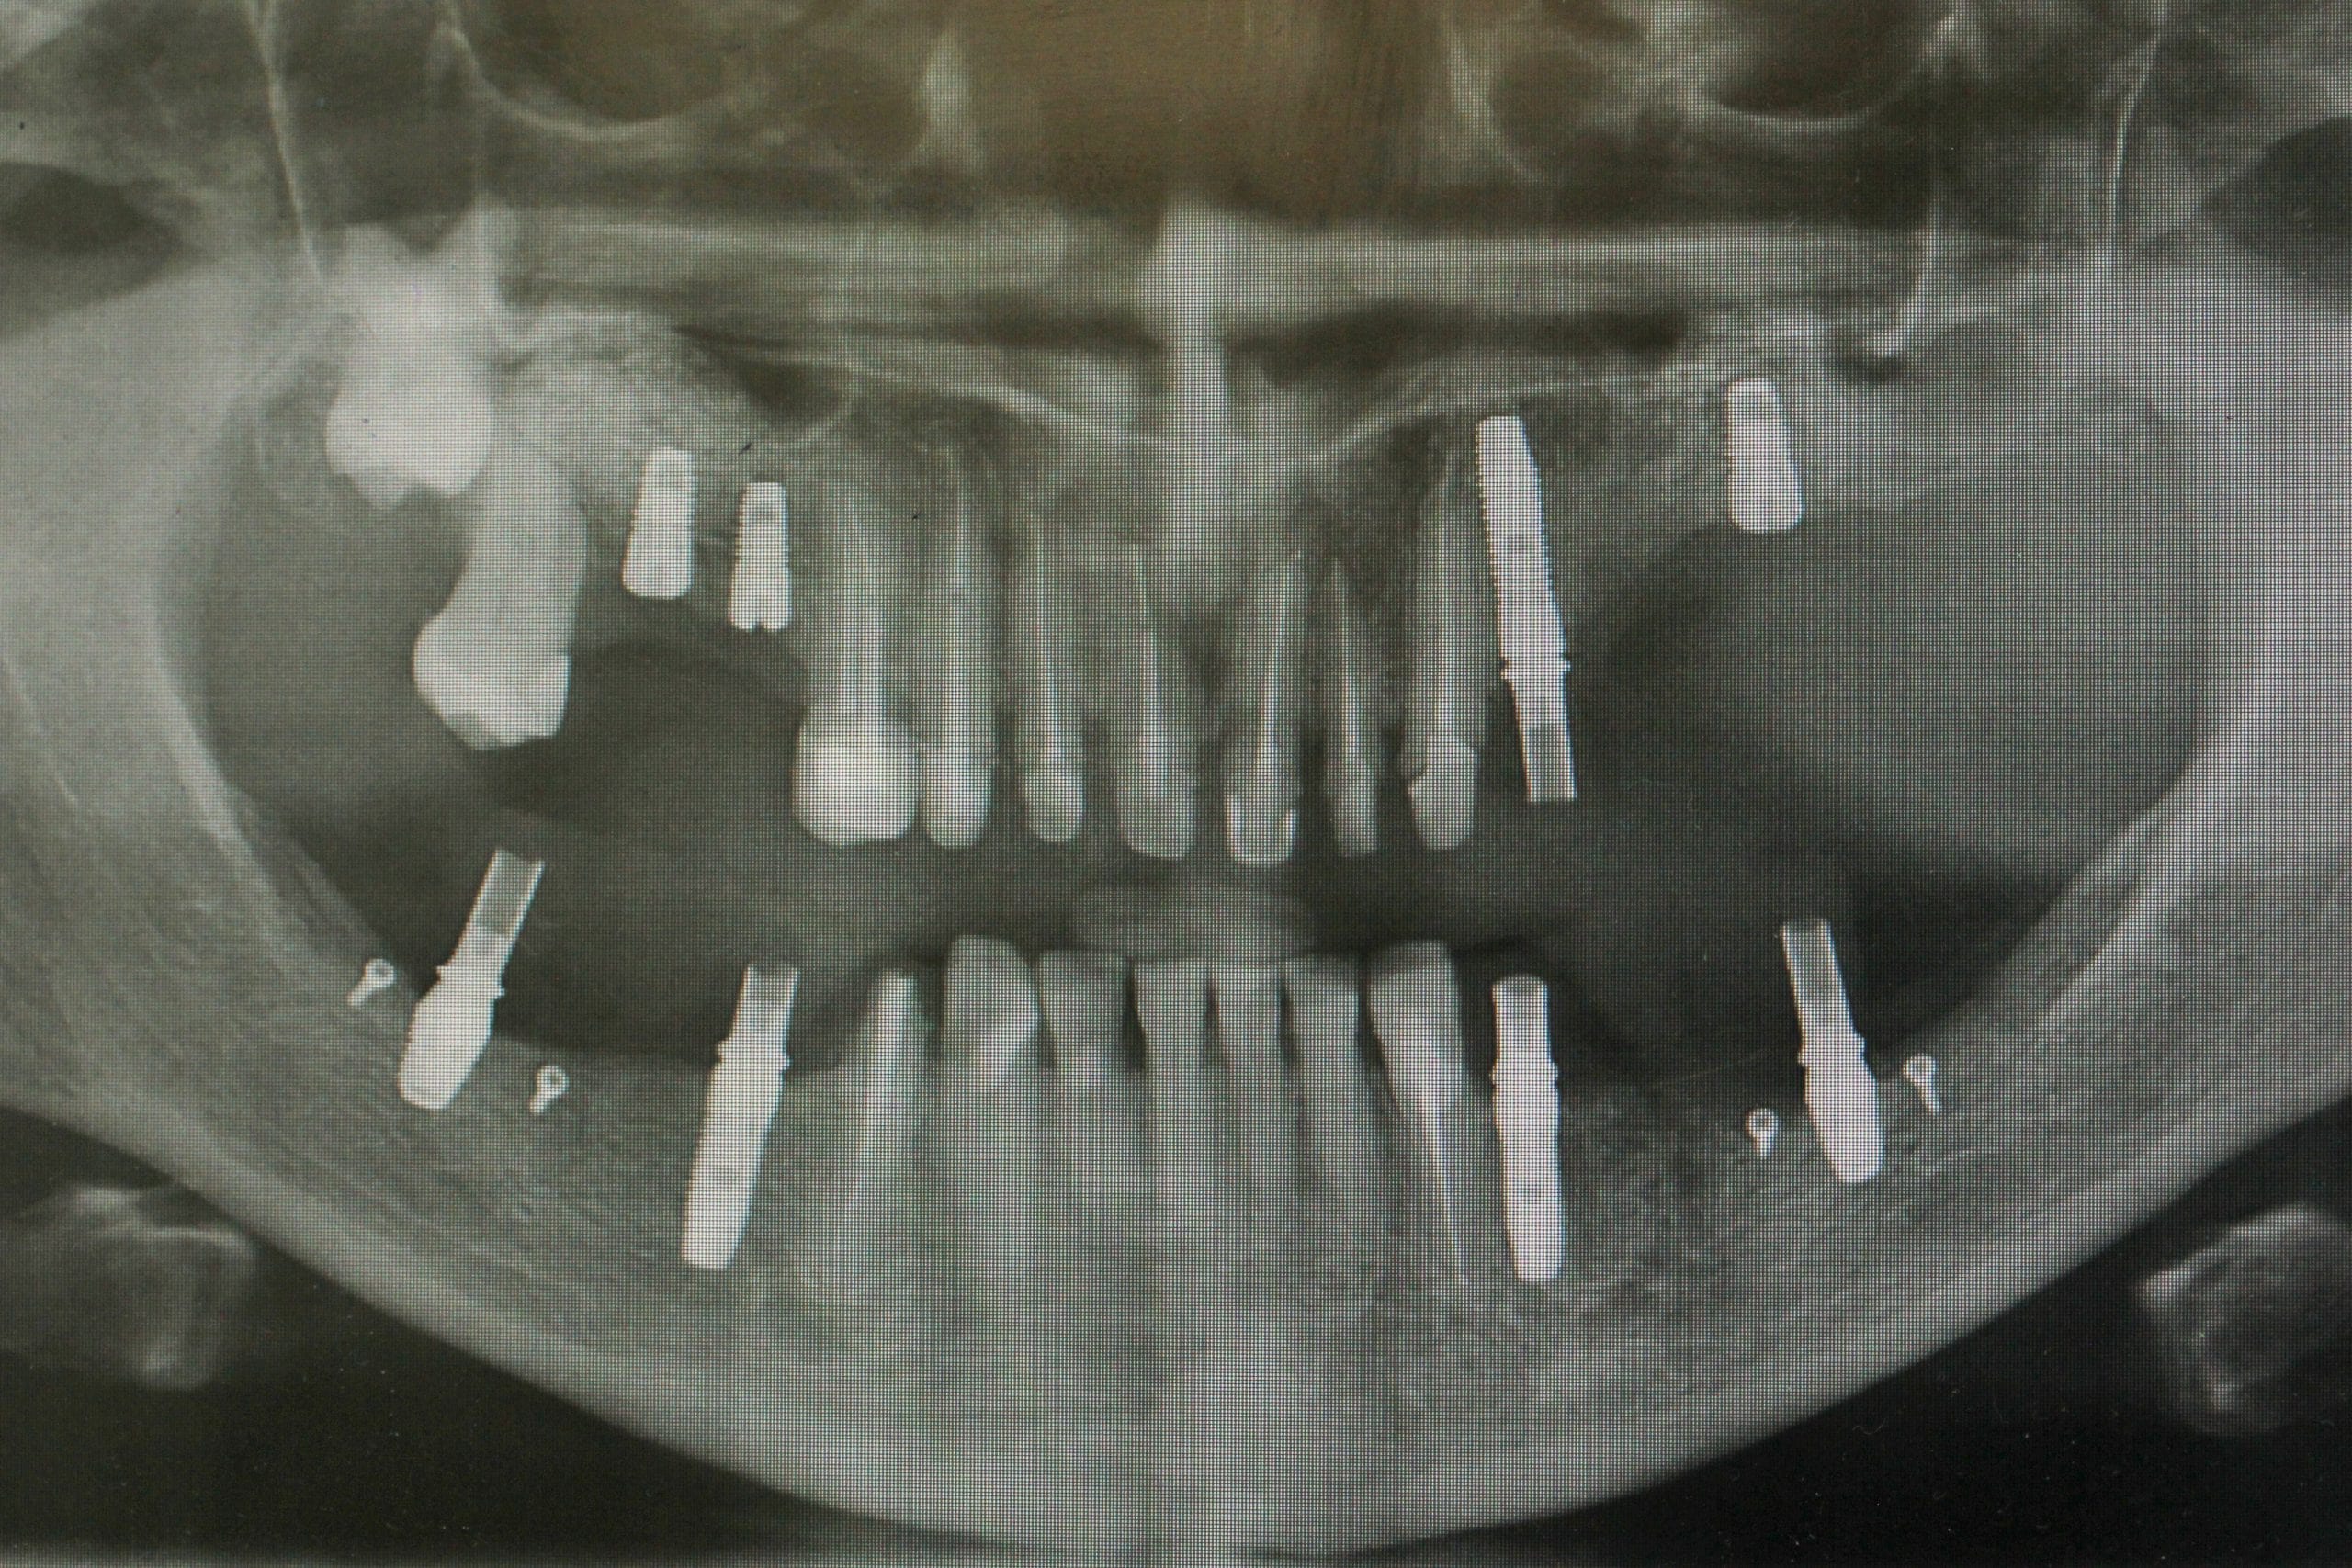

Пища под имплантом